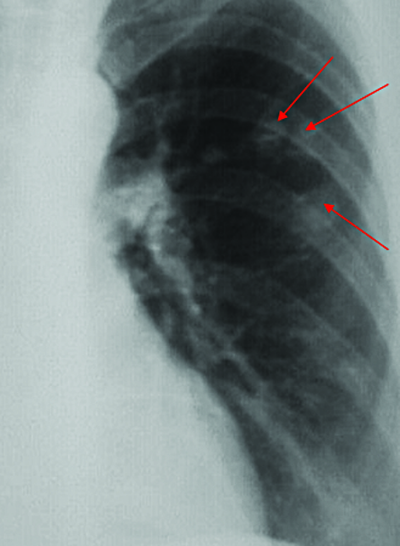

- На рентгенограмме очаговому туберкулёзу соответствует «синдром очагового затемнения». На ранних стадиях заболевания рентгенологически видны очаговые тени с нечёткими контурами, как результат воспалительной реакции в окружающей ткани. Очаги имеют среднюю или малую интенсивность. Они часто локализуются в верхних задних сегментах лёгких, и в области очагов может наблюдаться перифокальное воспаление. Это может привести к расширению корня лёгкого и его инфильтрации. На более поздних стадиях заболевания на рентгенограмме будут видны более чёткие и интенсивные очаги, иногда с наличие кальцинатов. Очаги обычно располагаются на фоне уже фиброзно изменённой ткани лёгких. Также могут быть выявлены кальцинаты в корнях лёгких[2][5][7].

- Определяемые рентгенологически очаги подразделяют на мелкие — до 3 мм, средние — до 6 мм и крупные — до 10 мм в диаметре[3].